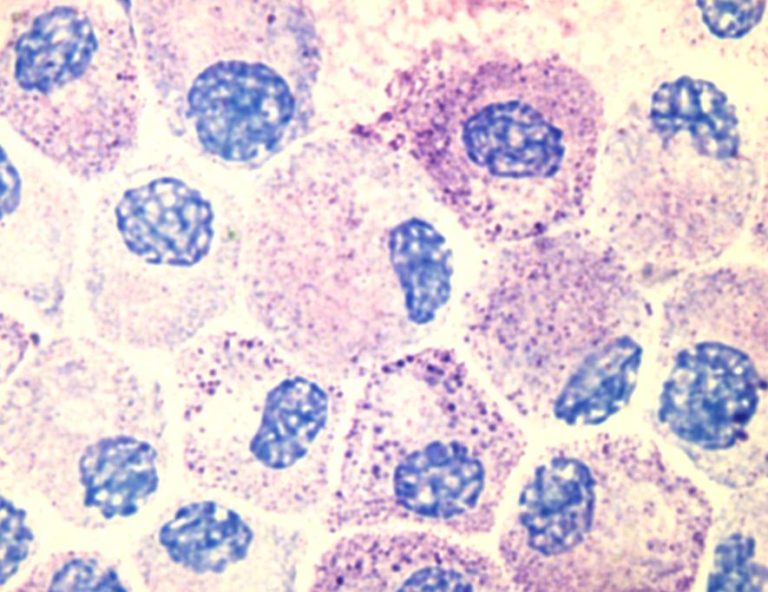

Los mastocitos son unas células del sistema inmune -el que ejerce la defensa natural contra las infecciones-, que se encuentran en varios tejidos del cuerpo, en particular debajo de la piel. Están implicados en la curación de heridas y cumplen una función importante en la respuesta que ofrece nuestro organismo a ciertas bacterias y parásitos. La proliferación o el aumento inusual de dichos mastocitos provoca diversas patologías que se agrupan bajo el nombre de mastocitosis, un conjunto de enfermedades raras que tienen como base común -en un 95% de los casos- la mutación genética.

Estas células están relacionan también con enfermedades de tipo alérgico o anafilaxias y aunque no es hereditaria sí que se han detectado casos de agregación familiar, tal y como explica Laura Sánchez, inmunóloga del Instituto de Estudios de Mastocitosis de Castilla-La Mancha, ubicado en el Hospital Virgen del Valle de la capital regional y Centro de Referencia Nacional de esta enfermedad -el segundo en Toledo junto al Hospital de Parapléjicos-.